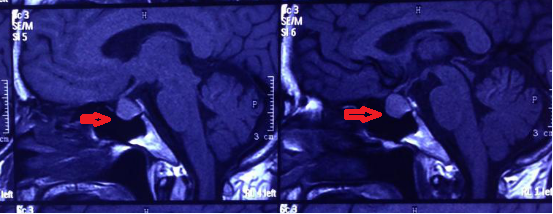

经神经外科专家组分析讨论病例,付旭东副主任决定采用创伤小、出血少的神经内镜技术切除肿瘤。这是神经外科的一项新微创技术。手术当日,在麻醉科、手术部的大力配合下,由神经外科一病区付旭东副主任操刀,由患者鼻孔插入直径仅4毫米的高清神经内镜,直视下避免颈内动脉、视神经、垂体柄等重要结构的损伤。经过2个多小时的细致暴露、分离和切除,顺利地全切了肿瘤,整个手术过程清晰地显示在巨大的高清电视屏幕上,流畅而精彩(图2、3、4)。

图2

图3

图4